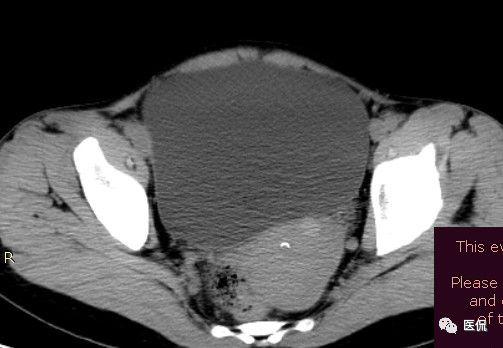

女 40岁 ,10年前做个剖腹产术。之后到现在一直感觉肚子疼,去很多医院做检查 诊断肠结核,经过反复抗结核治疗。病人10年瘦了几十斤。

腹腔内残留的纱布在人体内引起渗出或液化坏死并纤维包裹形成异物性脓肿(纱布瘤)。纱布瘤的影像特点:圆形或卵圆形肿块,较大,有完整包膜,薄壁,较少的情况下为厚壁,边界较完整,增强后薄膜可以持续强化。不同时期的纱布瘤可以有不同表现:早期(10个月或半年内)多表现为蜂窝状;2~5年内一般表现为囊性飘带状;10~20年之后则为实性软组织密度,包膜钙化呈钙化网状结构。手术过程中残留在人体内的医用纱布所形成的肿瘤样病变。

纱布团遗留腹腔后,首先由大网膜及邻近肠管将其紧密粘连并包裹,自肠管与纱布团粘连处开始逐渐向周围扩展产生纤维结缔组织包膜直至完全包住纱布团,该包膜血管丰富,充血明显,随时间延长逐渐向纱布团网眼内生长,使包膜逐渐增厚。机体还通过在包膜内产生大量异物巨细胞来围歼异物纱线,使包膜内侧形成脓肿。当包膜完全形成后,肠管与纱布团的粘连变的疏松,此时纱布团具有了一定的活动度。

腹腔内遗留纱布团的影像学表现,以B超较具特征性,其主要表现为:腹腔或盆腔内特殊率减的黑色包块,后方伴有扇形衰减的声影,上窄下宽,好似一“黑色大布”,早期包块内含有不规则光团或光点,随时间延长有缩小或消失,为纱布团内气体。CT的优势在于早期常表现为软组织密度的肿块,其内可见多少不等的气泡,随时间的延长气泡逐渐被吸收减少至消失,增强扫描可见包膜不同程度强化而内容物无强化。熟悉其影像学表现,可在术前作出明确诊断。